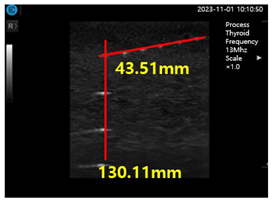

Figure 15a shows ultrasonic gel testing at various time intervals using the ATS-539 phantom. Figure 15b shows the sharpness of the image of the manufactured gelatin soft gel after storing it in alcohol and performing a sharpness test at 1 h intervals for 72 h. The results are presented in Figure 15b. In this paper, the experiment using a soft solid gel did not require IRB agreement. This research on the proposed gelatin soft solid gel showed its functionality to be better than that of ultrasonic gel, including on grayscale, echo, and color. This means that it can overcome the tissue density dead zone to increase high resolution performance. To help imaging accuracy, it is proven that gelatin soft gel, especially the soft solid gel, can replace ultrasonic gel to simplify disinfection and ensure permanent use. Image corrosion testing of gelatin soft solid gel for 30 min is shown in Figure 16a. Ultrasonic gels were tested at different times using an ATS-539 phantom, where the gel was soaked in ethanol for 72 h, as shown in Figure 16b. Afterwards, the gel’s condition was tested again. Finally, Figure 16c measures the imaging resolution of the gelatin soft tissue gel.

As shown in Figure 16, the individual values of the ultrasonic gel for grayscale, dead zone, vertical area, and horizontal area are 93.79 mm, 45.32 mm, 103.13 mm, and 83.86 mm, respectively. In contrast, the values for the soft solid gel are 105.64 mm in the grayscale, 34.48 mm in the dead zone, 141.0 mm in the vertical region, and 102.89 mm in the horizontal region. Therefore, the grayscale increased by 1.1 times, the dead zone remained the same, and the vertical zone increased by 1.2 times. As shown in Equation (12), the time value (T) in the horizontal zone was calculated by dividing that of the soft solid gel (x) by that of the American gel (y), resulting in a 1.2-fold increase. This calculation was performed by dividing the soft solid gel value by the corresponding ultrasonic gel value [25,26].